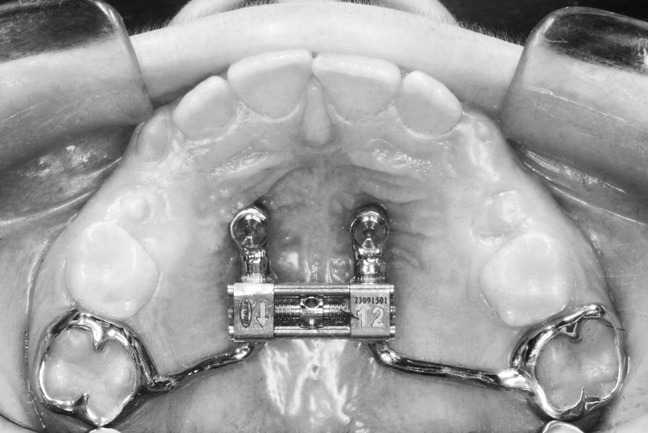

Anclaje esquelético MARPE guiado.

4. I INDEPENDENCIA/INTEGRACIÓN DIGITAL: Precisión con propósito. La tecnología solo tiene valor si mejora la eficiencia clínica. Aquí se aprende a planificar con MARPE, diseñar guías quirúrgicas 3D, optimizar alineadores in-office y flujos híbridos. El objetivo: que cada herramienta digital sirva para mejorar la eficiencia, no simplemente al marketing. “El futuro no está en más software, sino en el uso inteligente del que ya existe.”

MAPE en adultos y MISMARPE.

Clínico e investigador nos abrirá las puertas del MAPE en adultos con y sin asistencia quirúrgica con protocolos basados en la eficiencia clínica sin complicaciones.